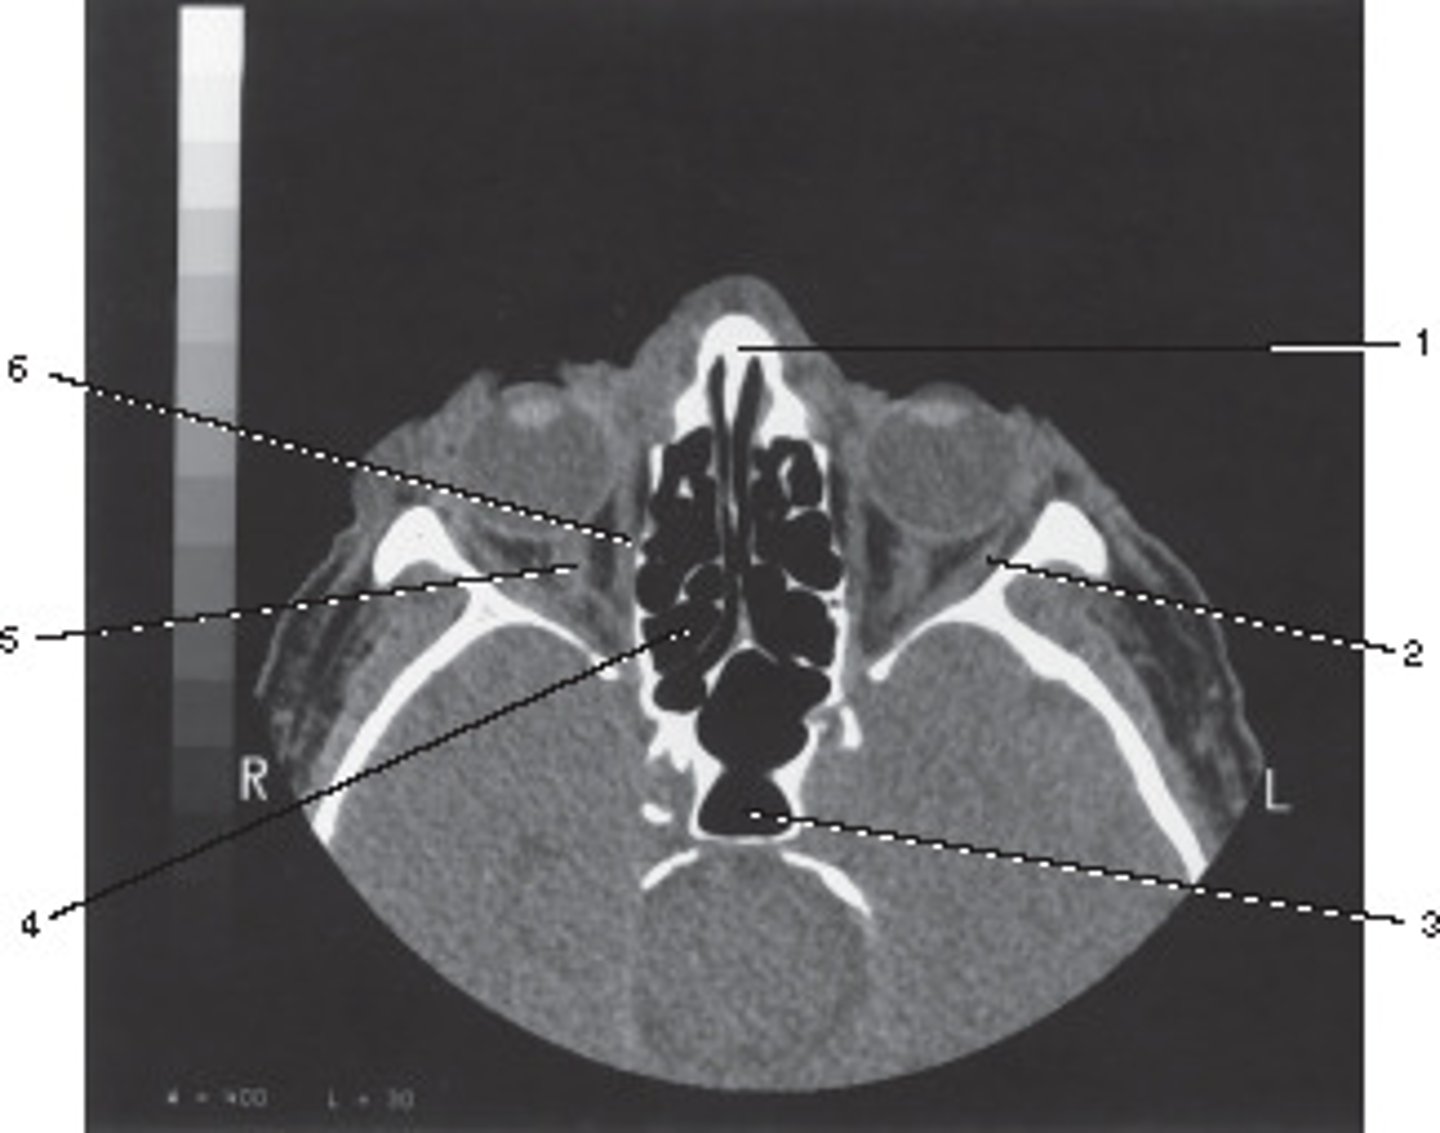

Number 2 corresponds to which of the following?

<p>Number 2 corresponds to which of the following?</p>

Number 5 corresponds to which of the following?

<p>Number 5 corresponds to which of the following?</p>

External Auditory Meatus

Number 3 corresponds to which of the following?

<p>Number 3 corresponds to which of the following?</p>

Oropharynx

Number 6 corresponds to which of the following?

<p>Number 6 corresponds to which of the following?</p>

Common Carotid Artery

Vertebral Artery